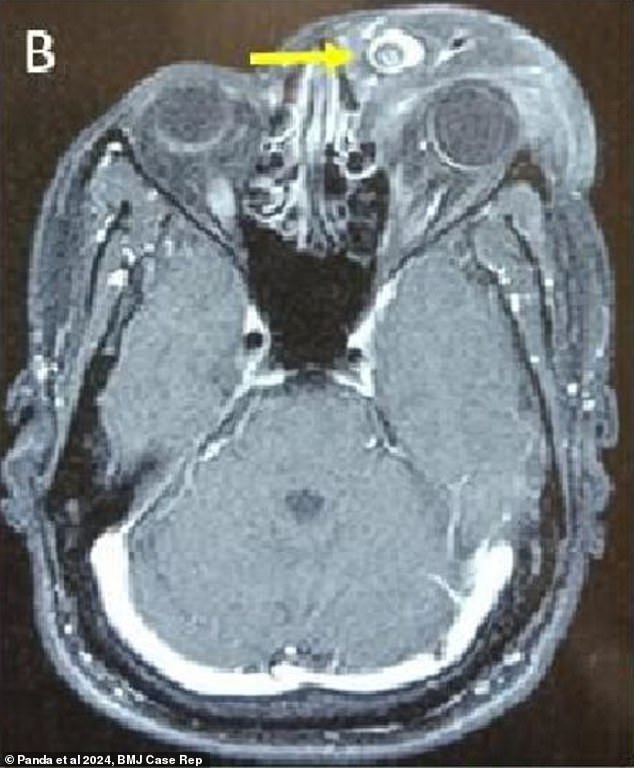

A brain scan before the surgery showed the mass, made of skin and blood tissue, that clung to the man’s left eyelid

The tumor, which was six inches in diameter and clung to a three inch long flap of eye tissue, was not cancerous, but still caused debilitating side effects.